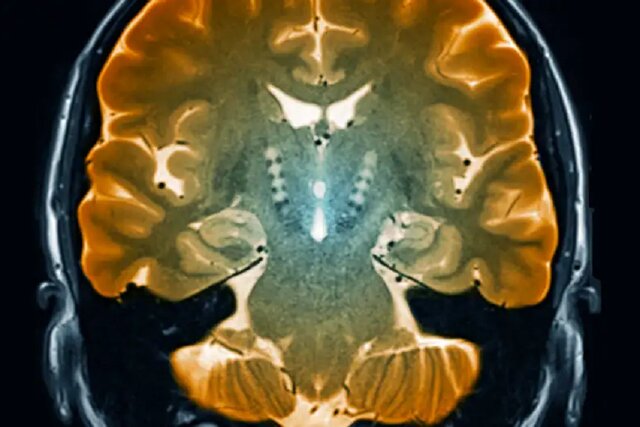

شناسایی سلول‌های مغزی مرتبط با بیماری پارکینسون

زیرگروهی از سلول‌های مغزی که در بیماری پارکینسون از بین می‌روند با استفاده از روشی جدید که نشان می‌دهد کدام ژن‌ها در هر سلول‌ فعال هستند، کشف شده است.

به گزارش ایسنا و به نقل از نیوساینتیست، دهه‌هاست که می‌دانیم بیماری پارکینسون که یک بیماری پیش‌رونده است و منجر به لرزش اندام‌ها و مشکلات حرکتی می‌شود، با مرگ تدریجی سلول‌های بخشی از مغز به نام جسم سیاه(substantia nigra) ارتباط دارد. این سلول‌ها یک ماده شیمیایی به نام دوپامین می‌سازند که در کنترل حرکت نقش دارد اما هویت دقیق این سلول‌ها تاکنون مشخص نشده بود.